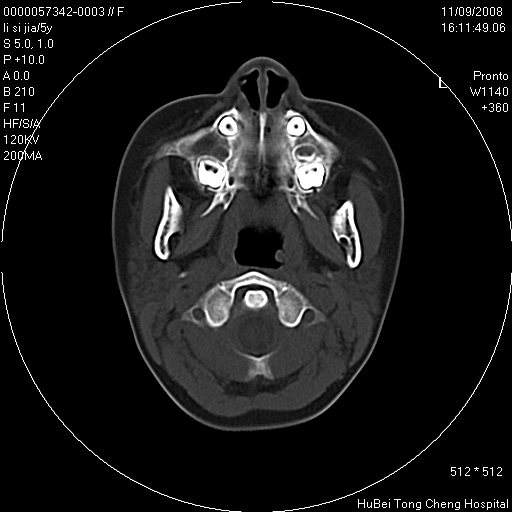

患儿 女,5岁。鼻塞、流涕2年余。

临床诊断:慢性副鼻窦炎?

副鼻窦ct轴位平扫(层厚、层距均为5mm),图像如下:

双侧上颌窦\\筛窦及蝶窦内均可见多量软组织密度影,结合病史支持考虑慢性全鼻窦炎

双侧上颌窦、筛窦及蝶窦内均可见粘膜增厚,结合病史支持考虑慢性全付鼻窦炎,腺样体肥大。